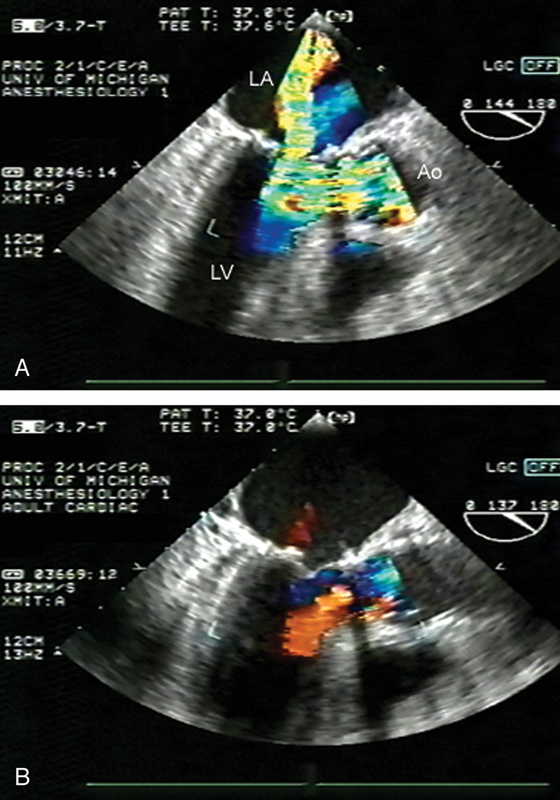

فحوصات تشخيصية لبعض امراض القلب والشرايين التاجية